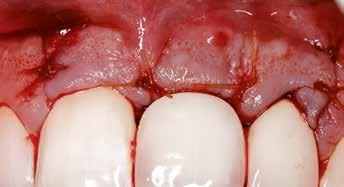

1. ábra: A műtét előtti szituáció, megfigyelhető az implantátumok közötti konkáv terület, ahova könnyen beragad az ételmaradék, és könnyen kialakul a periimplantitis.

Egy 47 éves páciens jelentkezett nálunk egy alsó, hátsó foghiánnyal, ahol jelentős csontfelszívódást tapasztaltunk a moláris fogak korábbi eltávolítása miatt (1. ábra). Két implantátum körül is volt ínyrecesszió, illetve a keratinizált íny mennyisége minimális volt (kevesebb, mint 1 mm). 4 hónappal az implantációt követően ínykorrekciót végeztünk.